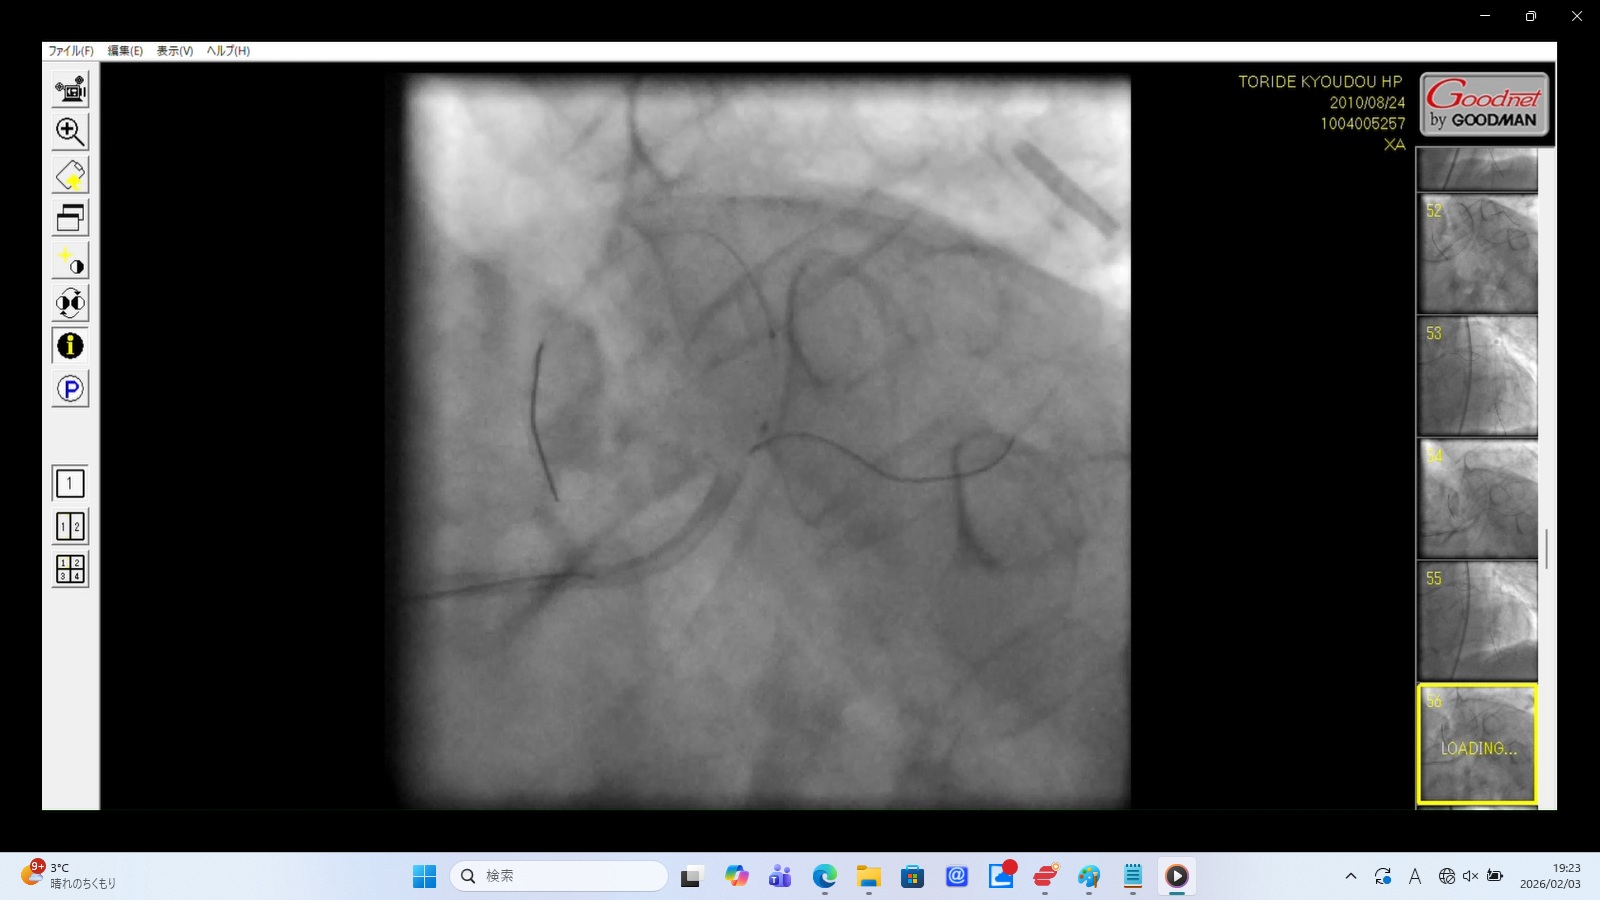

また23:15~23:25頃、「血栓吸引」との記載があるが、その時間帯を含む23:08~23:26の18分間の動画が存在しない。 その後の動画では左冠動脈主幹部が解離・損傷。そのリアルタイムの証拠が抜き取られた可能性がある。 - 8月24日~25日:カテーテル手技の大事故(冠動脈損傷・閉塞・穿孔)

左前下行枝解離・穿孔、左冠動脈主幹部解離・損傷・完全閉塞、ステント様人工物の血管外脱落などの所見あり。 術者の岩井利之医師は「治療は成功した」と偽り、これらの大事故・大損傷を隠蔽した。救命のためには心臓血管外科での緊急手術が必要な状態であったはずだが、医師らはその手配をせず放置した。

左冠動脈主幹部解離(真腔と偽腔の併存)と血管外漏出

22時35分に開始され、右橈骨動脈にガイドワイヤーを挿入して手技が開始されたが、 冠動脈にアプローチできず、右大腿動脈から挿入された。その間、アプローチが失敗した時間帯のPCI画像が 存在せず、ここで大事故を起こした証拠であるこの間の画像が抜き取られた可能性が疑われる。 PCIは3時間と長時間を要し、その間の放射線被曝量も人体に深刻な影響を与えるほど大量であった。 PCIの動画を確認すると左冠動脈主幹部解離・損傷・閉塞、左冠動脈前下行枝解離・穿孔、 左回旋枝への血栓閉塞、ステント様人工物の血管外落下など多数の致命的な大事故が認められた。 救命のためには心臓血管外科での開胸手術が必要のはずであったが、PCI終了後、医師は遺族に対して「治療は無事成功した」としてこの大事故を隠蔽し、心臓血管外科への手配をせずに放置し談笑していた。